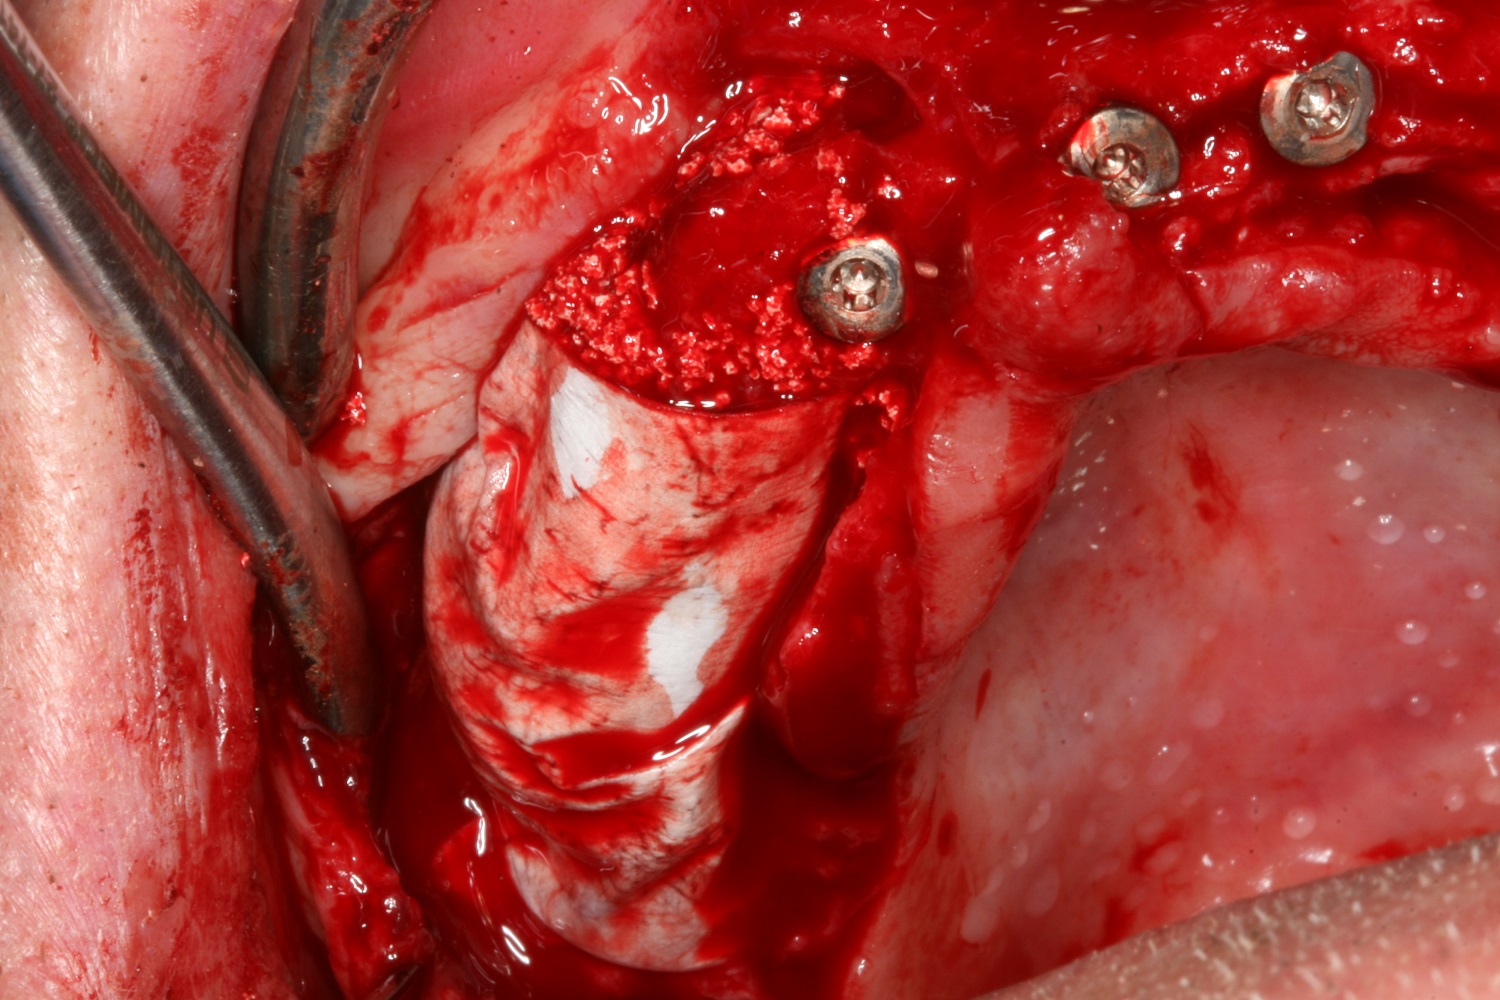

04/10 - Lateral deposition of maxresorb® to prevent resorption of the vestibular wallCircular bone splitting with maxresorb® & collprotect® membrane - PD Dr. J. Neugebauer

Surgical presentation of the alveolar ridge with reduced amount of horizontal bone available